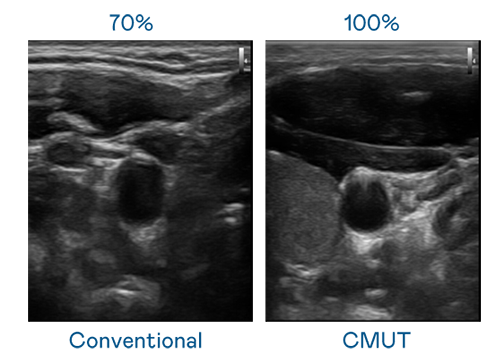

CMUT 技术是一种用电容式微机电元件来产生超音波讯号的技术。与传统 PZT 压电式技术相比,CMUT 频宽增加 30%,更宽频的超音波讯号让影像解析度大幅提升,是实现高影像品质医疗超音波扫描、促进精准医疗发展的关键技术。

大频宽带来超清晰影像

超音波影像的解析度高低,首先取决于探头能发出的讯号频宽。免费的情网站推荐 CMUT 可提供高清晰的超音波讯号,提供高频宽、高灵敏度、影像纹理细节更高的超音波影像,协助医护人员缩短影像判读时间及利用精准的医疗影像进行诊断。